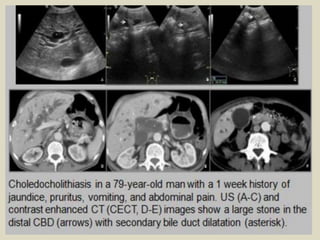

Choledocholithiasis A 35 years old female presented with jaundice. (a) US imaging

shows a dilated CBD obstructed by a stone with a posterior acoustic shadow. (b) CT

(coronal oblique reconstruction without injection) shows the dilatation of the CBD

Choledocholithiasis A 35years old female presented with jaundice. (a) US imaging shows a dilated CBD obstructed by a stone with a posterior acoustic shadow. (b) CT (coronal oblique reconstruction without injection) shows the dilatation of the CBD